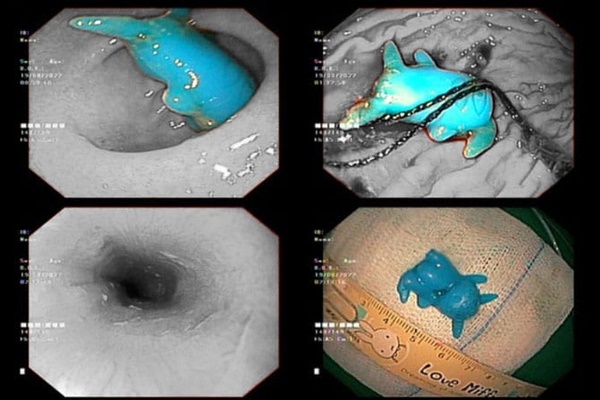

Dị vật mắc kẹt ở thực quản bệnh nhi. Ảnh: BVCC

Qua thăm khám, dị vật được phát hiện kẹt ở 1/3 giữa thực quản. Hình thù đồ chơi có sừng dài dễ đâm thủng thực quản và gây khó khăn trong quá trình xử trí.

Sau khi tiến hành nội soi cấp cứu trong đêm, dị vật được lấy ra và sức khỏe bệnh nhi đã ổn định.